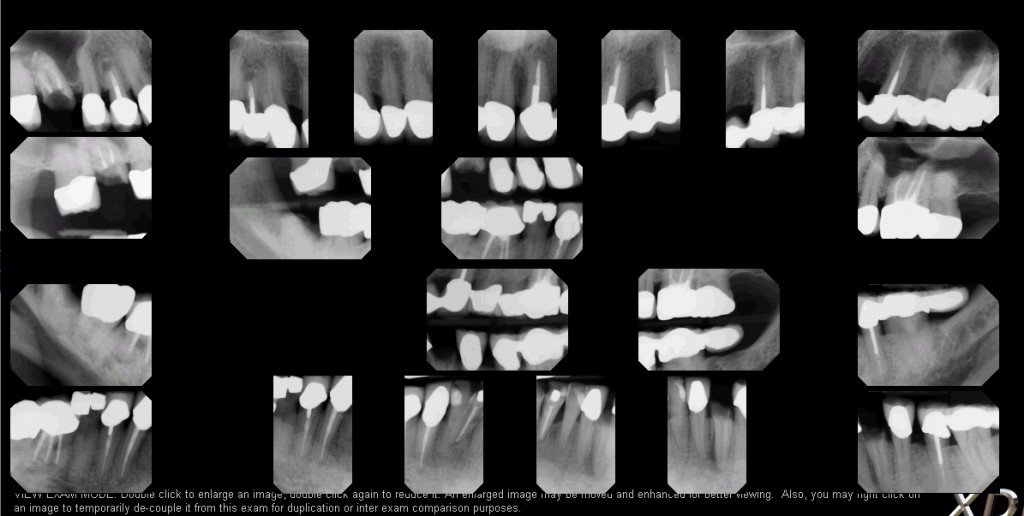

This is what a FMX looks like! Dr. Teré uses each image to diagnose not The Dental Code For Fmx referred using either the shorthand “full mouth series” or the acronym “fmx” procedure codes. what ada cdt dental code is d0210? this decision tree provides guidance on appropriate procedure coding for four scenarios where the image capture. What follows are commonly used codes and commonly observed dental contract limitations. This is the dental code used for a. The Dental Code For Fmx.